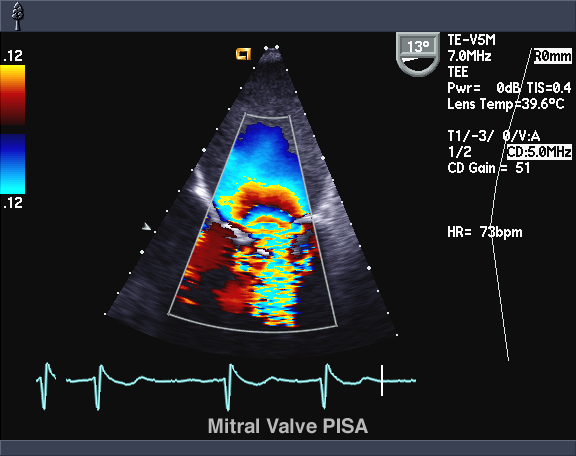

- Триплексным, для получения данных в цветном виде. Этот вид исследования используется для отслеживания движения эритроцитов и получения развернутой картины беременности.

Оценить скорость кровотока сосудов пуповины, матки и плодовой части плаценты позволяет допплерометрия. В плановом порядке ее назначают всем беременным на сроке 30–34 недели.

Доплер показывает, как течет кровь по сосудам измеряет скорость потока крови. УЗДГ также может быть полезно для установки диаметра сосуда, а также величины стеноза (закупорки) кровеносного сосуда. Традиционное УЗИ использует безболезненные звуковые волны, неслышимые человеческим ухом, которые отражаются от сосудов.

Допплер УЗИ при беременности (допплерометрия, допплерография) позволяет исследовать кровоток у плода, а также в матке и плаценте. Полученная информация дает возможность оценить, достаточное ли количество питательных веществ получает ребенок.